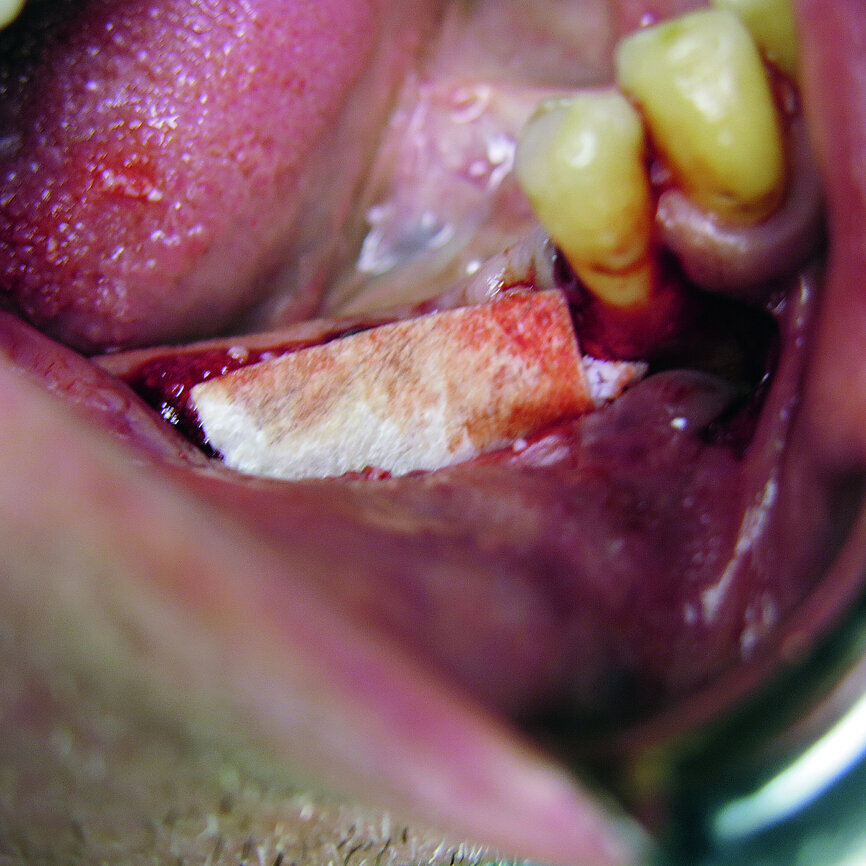

Fig. 10: 3-D augmentation using NanoBone.

In our cases NanoBone, pericard membrane (imperiOs) and autologous bone chips were used for augmentation. NanoBone is an efficient nano-structure nano-crystalline hydroxyapatite embedded in a highly porous silica gel matrix. NanoBone is a safe product and stimulates the formation of collagen and bone. As an effect, many osteoblasts are seen in the early stage of regeneration. NanoBone has been on the market three years in the form of putty. NanoBone putty has a high consistency and is optimal for use to rebuild vertical bone. In general, no additional membranes are necessary. Its special structure results in rapid bone formation. As the osteoclasts resorb the granules, NanoBone is completely substituted by bone and no foreign substances will influence natural biomechanics.

Alternatively, NanoBone block material is now on the market and is a safe and rapid solution for block augmentation. Animal studies have shown that it induces quick bone formation. It offers an alternative to autogenous bone blocks for improving the implant bed in the case of vertical and horizontal bone deficits. In two patients with defects of the lower jaw, NanoBone block was used to optimise horizontal defects. NanoBone material was fixed with CAMLOG screws and a collagen membrane was used (RESORBA Medical).